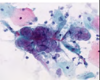

What is a

definitive diagnosis for HSV1 Herpes simplex

HSV‐ Cytology‐

Papanicolaou Stain

(PAP)

HSV‐ Histopathology

❏ Molding

❏ Margination

❏ Multinucleation

❏ Also Tzanck cells